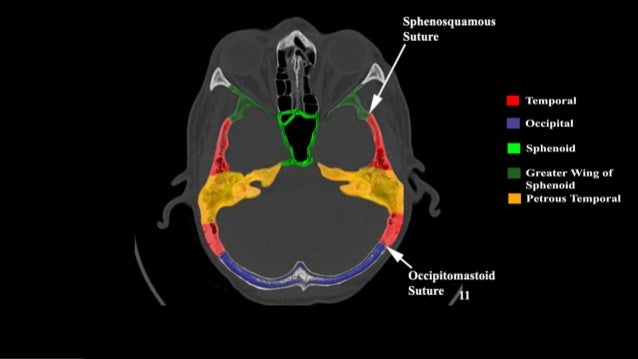

Overview Of Skull Base Anatomy

They are highly irregular bones with extensive muscular attachments and articulations with surrounding bones. In this review we present the normal axial and coronal anatomy of the temporal bone by scrolling through the images. The temporal bones are a pair of bilateral symmetrical bones that constitute a large portion of the lateral wall and base of the skull.

The temporal bones comprise the lateral skull base forming portions of the middle and posterior fossae. Each temporal bone is composed of five osseous parts. This atlas allows you to scroll through ct slices of the temporal bone in four different planes.